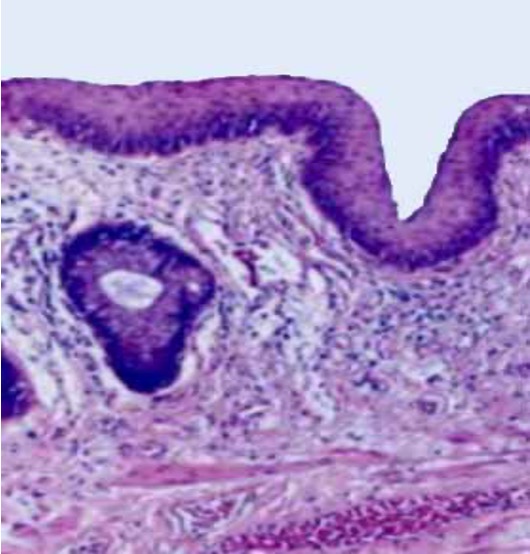

External Anal Margin

Alternate 3 AcidsThe external anal margin is generally thicker and drier compared to the rest of the perianal skin

This area has a tougher skin texture, which helps protect it from friction and abrasion

The external anal margin is generally thicker and drier compared to the rest of the perianal skin